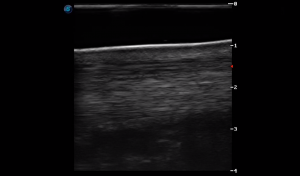

SIMON Ultrasound Database

This ultrasound database is a free resource for students and doctors!

Our collection includes videos of dogs, cats, horses, cows, humans, and many other species!